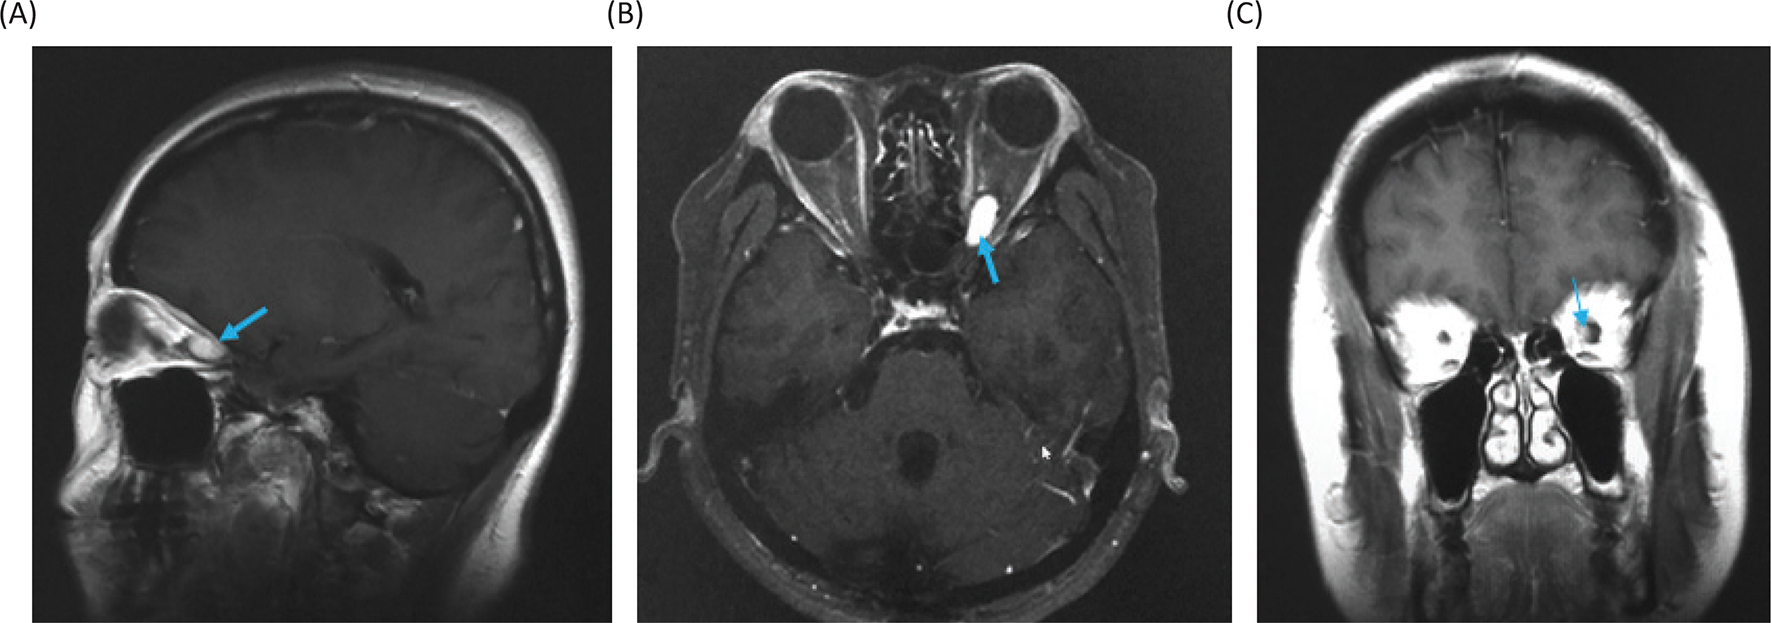

Magnetic resonance imaging (MRI) of the head showed a Gd-enhanced well-circumscribed mass on the left retrobulbar optic nerve in the orbital, and three-dimensional MRI showed the tumor enveloped the left optic nerve (Figure 4).

Fig 4

Figure 4. Magnetic resonance images before radiosurgery. (A) Gadolinium (Gd)-enhanced T1-weighted image, sagittal. (B) Gd-enhanced T1-weighted image, axial. (C) Gd-enhanced T1-weighted image, coronal. Yellow arrows show the tumor. (D) Three-dimensional planning MRI for radiosurgery. The light blue color indicates the tumor enveloping the optic nerve.